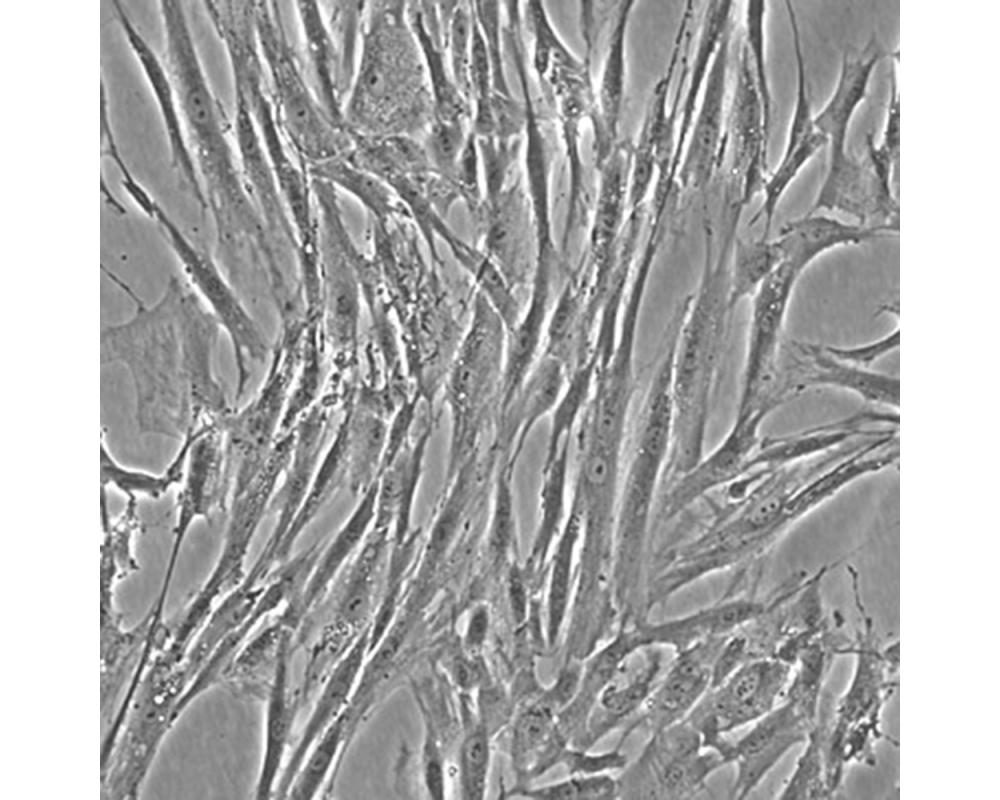

產(chǎn)品名稱(chēng) Hs 606.T

中文名稱(chēng) 人乳腺癌細(xì)胞

組織來(lái)源 乳腺癌;女性

生長(zhǎng)特性 貼壁

培養(yǎng)基 H-DMEM,90%;FBS,10%;雙抗。

培養(yǎng)條件 Atmosphere: Air, 95%; CO2, 5%。Temperature: 37℃